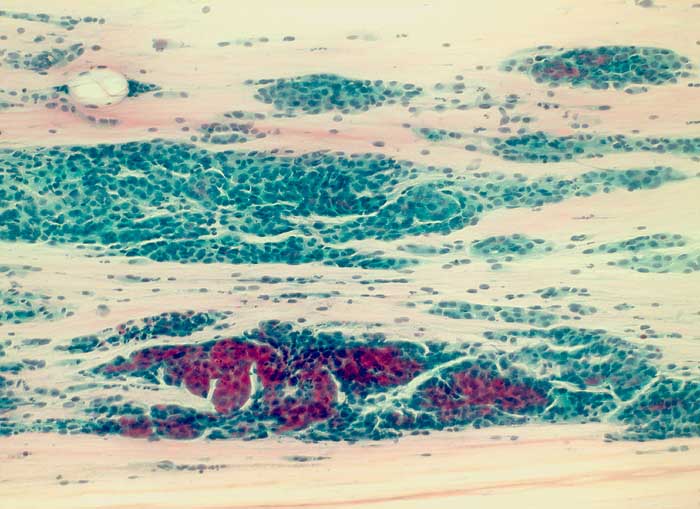

Die Zellkerne der serösen Adenokarzinome sind in den meisten Fällen hochgradig atypisch. Das Zellbild gleicht entsprechend demjenigen eines wenig differenzierten endometrioiden Adenokarzinoms. Da das seröse Karzinom anders als das endometrioide Karzinom nicht Folge eines Hyperöstrogenismus ist, zeigen die meist postmenopausalen Patientinnen keinen hohen Aufbau des Vaginalepithels im PC-Abstrich.